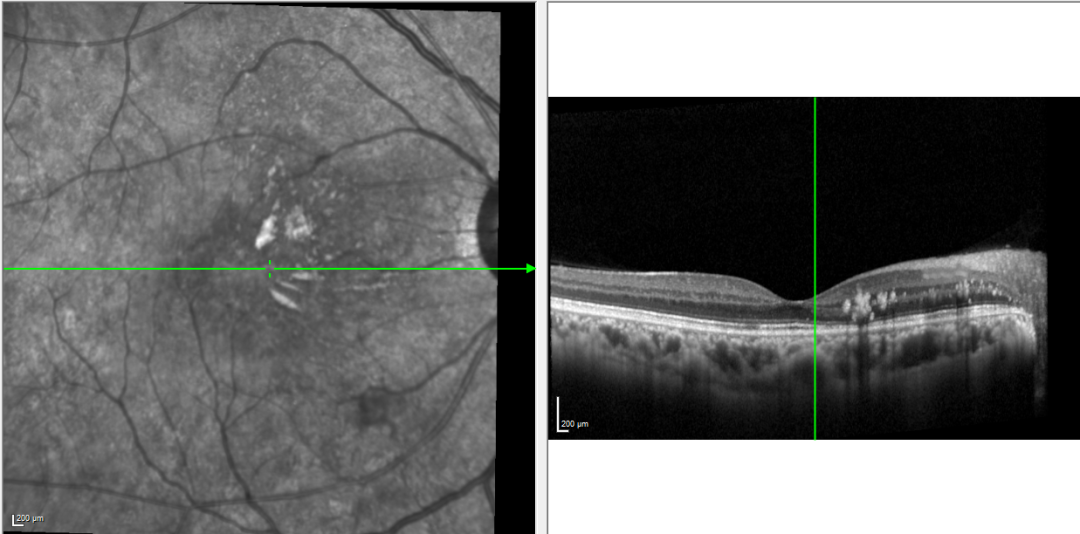

OCT提示:双眼黄斑区视网膜可见团块状高反射,右眼黄斑区视网膜神经上皮层浅脱离,层间积液

提示:眼底出血基本吸收,视网膜下积液基本吸收,病情明显好转